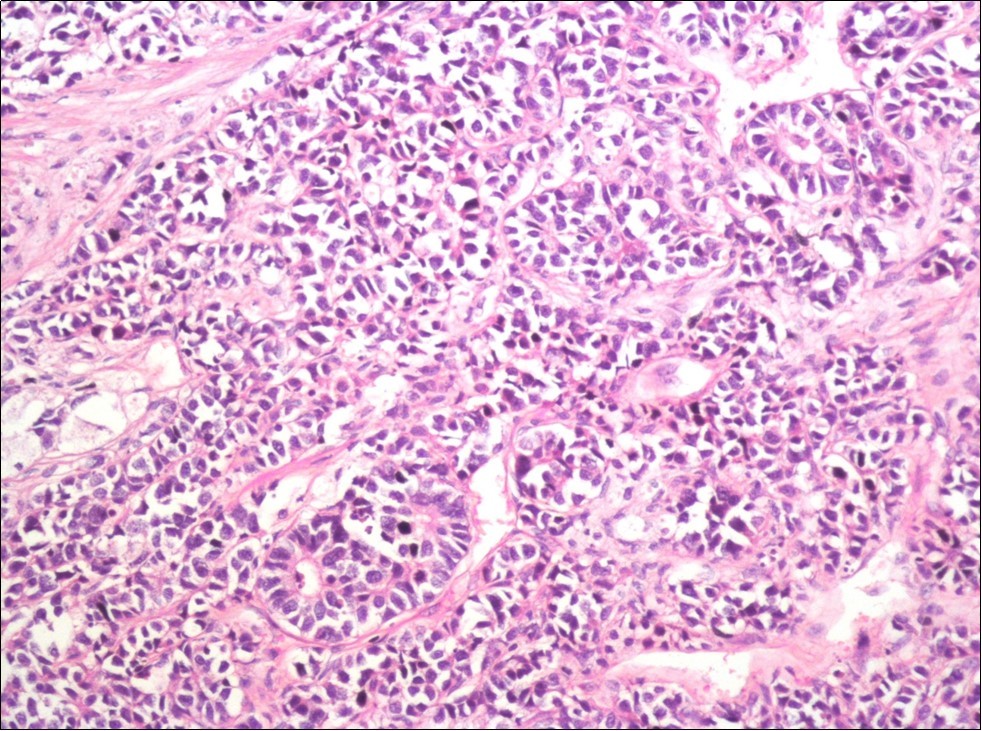

A 73-year-old male patient was admitted to our outpatient clinic with acute urinary retention. Digital rectal examination was normal. The PSA value was 1.81 ng/dl. Prostate size was 101 cc. Since the PSA value and digital rectal examination were normal, no biopsy was taken. Ultrasonography showed bilaterally ureterohydronephrosis. The creatinine level was 2.89 mg/dl. Hypertension has been presented as a comorbidity. An 18 Fr Foley catheter was inserted and alpha-blockers and 5-α reductase inhibitor medication was given. Creatinine level decreased to 0.91 mg/dl after one week. When the patient's catheter was pulled out, he could not urinate again. A catheter was inserted and waited one week more. After one week, the patient was unable to urinate again. The operation was decided due to this recurrent urinary retention. Because of prostate size was 101 cc and prostatic urethra was long, open prostatectomy was decided. When the prostate was removed during the operation, it was evaluated that the left side and the lower side were adhered to surrounding tissue. The prostate was removed as an en bloc. The catheter was removed after 5 days. The pathology of the patient has been reported as pure small cell prostate carcinoma. On the microscopic examination, the tumor was heavily infiltrated into the prostate parenchyma (Figure 1). Tumor cells were consist of atypical small-medium sized, mitotically active cells with a high nuclear to cytoplasmic ratio, hyperchromatic nucleus, nuclear molding, and inconspicuous nucleoli (Figure 2). On the immunohistochemically examination of synaptophysin showed diffusely and strong positivity while chromogranin A showed focal weak positivity with the absence of staining for PSA (Figure 3). Ki67 proliferative index was equal to 90% of the tumor cells (Figure 4). The results confirmed the diagnosis of prostatic small cell carcinoma. Metastatic lymph nodes were detected in the right perirectal region with metastatic multiple lymph nodes in the bilateral external iliac region, more on the left than in the PET CT. No metastasis was detected in the brain MRI and thorax computed tomography. Four cycles of etoposide and cisplatin chemotherapy were administered to the patient. Control PET CT taken after chemotherapy showed a significant decrease in size and metabolic activity of the right obturator and lymph nodes in the right perirectal area. The size and metabolic character of the left obturator, left external iliac and common iliac lymph nodes were increased. After a month, patient admitted to emergency outpatient clinic with left flank pain. There was an 8-cm mass in retroperitoneal area in the computed tomography. Supportive treatment was started because the patient could not tolerate chemotherapy. The masses reached to 13x11cm and fulfilled the retroperitoneal area. Multiple lung metastases were seen. The patient died 13 months later after the first diagnosis.

Figure 1.Infiltration of the tumor cells between prostatic ducts (H&E, x40)